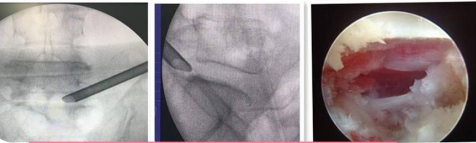

UBE(Unilateral Biportal Endscopic,單側(cè)雙通道內(nèi)鏡技術(shù))是新興的一種脊柱外科微創(chuàng)技術(shù),被廣泛應(yīng)用于脊柱退行性疾病(包括腰椎間盤突出癥、腰椎滑脫、腰椎管狹窄、頸椎病等)的治療,收到了較好的臨床效果。UBE手術(shù)具有視野清晰、創(chuàng)傷小、出血少、效率高、療效好及恢復(fù)快的特點(diǎn)。我院在重慶市較早開展此項(xiàng)技術(shù),多次通過手術(shù)直播、學(xué)術(shù)講座和實(shí)操培訓(xùn)形式充分展示此項(xiàng)技術(shù)。

94f27ffa5ca14b1f82cb4ee9d26b4a66.Png

4f400e6adfaa40aa970dedaf1200326f.Png